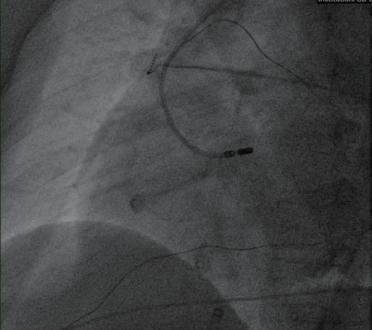

(4)室早起源于主动脉窦、左心室或左心室流出道的患者可能需要穿刺股动脉进行手术,必要时需进行冠状动脉造影,明确消融靶点,避开冠状动脉后,再放电消融至室早终止(图2-3-2)。

图2-3-2 股动脉入路行左心室来源室早消融